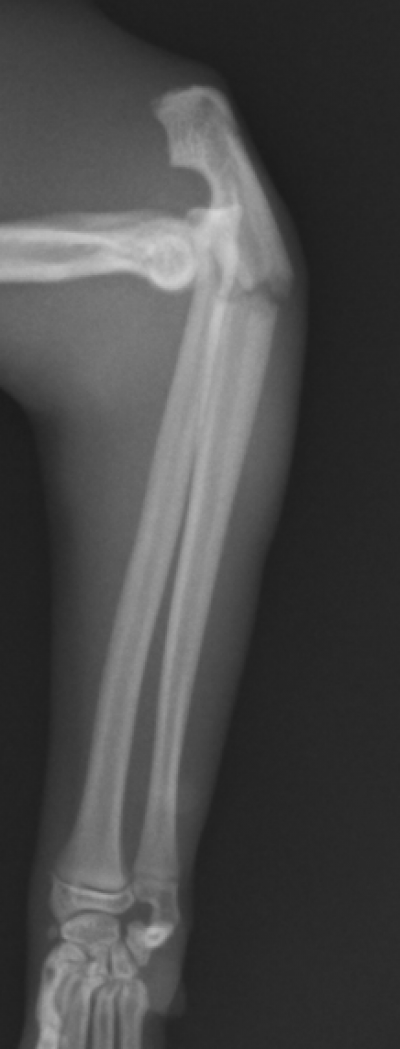

尺骨幹部骨折とモンテギア脱臼骨折

猫の モンテジア骨折 の手術 整形外科 やまと動物病院やまと動物病院

前腕の骨幹部骨折 一般社団法人 日本骨折治療学会 骨折の解説